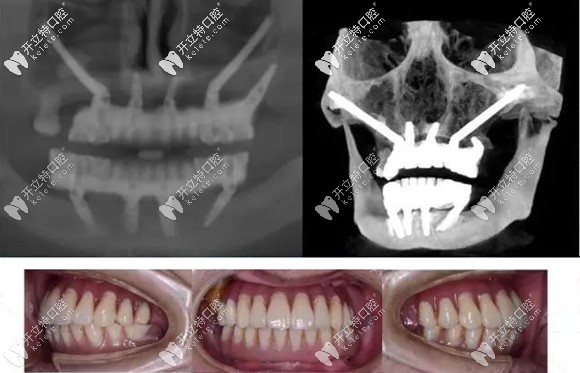

簡(jiǎn)單來(lái)說(shuō),把種植體植入到顴骨和翼板骨上的種植方法,就叫做穿顴穿翼種植技術(shù)。

對(duì)于上頜骨切除、上頜骨重度萎縮,做常規(guī)的上頜竇內(nèi)外提升,也沒(méi)有辦法達(dá)到種植條件的無(wú)牙頜患者,就需要向頜面部的顴骨和翼板找可植入種植體的骨頭。

而這部分的骨頭也適合作為種植位點(diǎn),它不會(huì)像牙槽骨那樣萎縮吸收。但是,也由于這個(gè)位置比較靠上,所以,手術(shù)的難度也就大大增加了,一般的口腔機(jī)構(gòu)都無(wú)法進(jìn)行這項(xiàng)手術(shù)。

穿顴穿翼就是種植體植入到顴骨和翼板骨上的種植方法